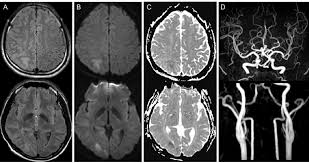

"MRA(Magnetic Resonance Angiography, 자기공명 혈관촬영)"는 MRI를 기반으로 혈관 구조를 영상화한 검사입니다.

- 원리: MRI 기술을 활용하여 혈류 신호를 강조하고, 혈관과 주변 조직을 분리하여 영상화

- 주요 특징: 동맥, 정맥, 혈관 협착, 동맥류 등 혈관 상태 평가에 특화

- 조영제 사용 여부: 일부 경우 가돌리늄 기반 조영제를 사용해 혈류를 더 명확하게 관찰

MRA는 심혈관 질환, 뇌혈관 질환, 말초 혈관 질환 등 혈관 이상 진단에 특히 유용합니다.

MRI와 MRA는 모두 자기공명 기반 영상이지만 목적이 다릅니다.

- MRI: 장기, 조직, 연조직의 구조적 이상 확인

- MRA: 혈관 상태 및 혈류 이상 확인

즉, MRI는 조직 중심, MRA는 혈관 중심 진단이 기본 목표입니다.